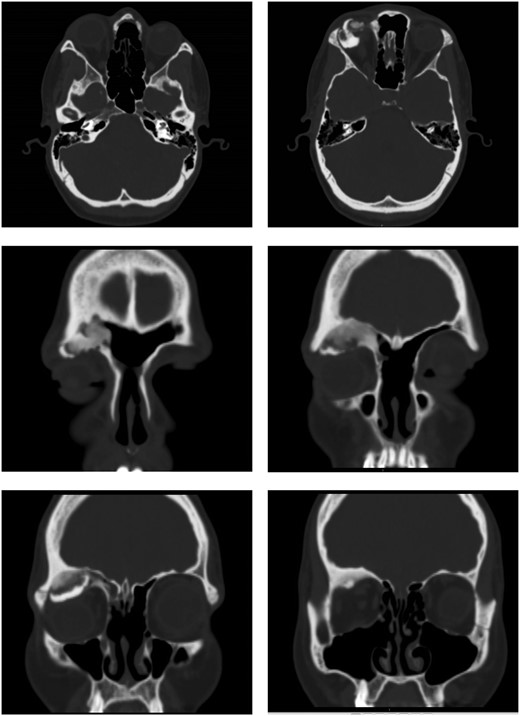

She underwent an external bicoronal approach, frontal sinusotomy with an osteoplastic flap. The frontal sinus was opened and the OF shelled out, including the orbital roof connection. A 3 cm × 2.5 cm defect in the orbital roof, was closed with an irradiated cadaveric rib (Tutoplast ®) graft fashioned to size (Fig. 2). This was overlaid with a pericranial flap. An osteoplastic flap was used to close the frontal sinusotomy, secured with screws.

Combined endoscopic and bicoronal approach with the cadaveric rib graft cut to size to fit and repair the orbital floor defect.